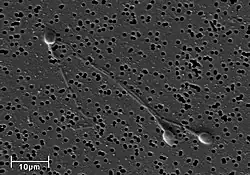

Electron micrograph of human spermatozoa magnified 3140 times. -

A human sperm cell consists of a flat, disc shaped head approximately 5.1 by 3.1 μm (0.20 by 0.12 mils), and a tail, known as a flagellum 50 μm (2.0 mils) long.[4] The flagellum propels the sperm cell at about 1 to 3 millimetres per minute (0.66 to 1.97 mils per second).[5] Sperm have an olfactory guidance mechanism, and after reaching the fallopian tubes, must undergo a period of capacitation before penetration of the ovum.[6]